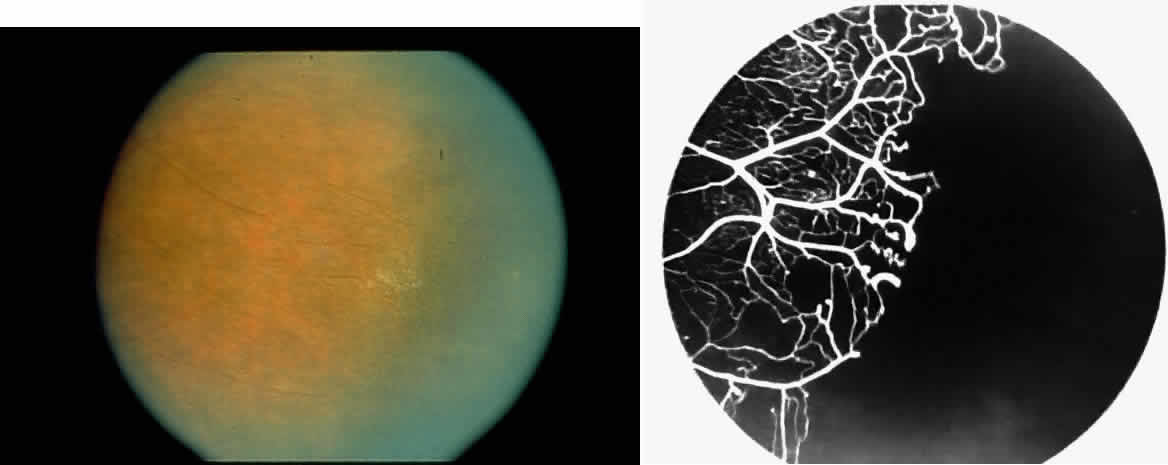

STAGE I: PERIPHERAL ARTERIOLAR OCCLUSIONS. This stage may be further subdivided into three grades: grade I, narrowing of the peripheral arterioles with tortuosity and abnormal looping of the peripheral venules; grade II, tortuosity, dilation, and microaneurysmal formation in the capillary network; and grade III, occlusion of the peripheral capillaries and arterioles.83

The occluded arterioles may be invisible or may have a “silver-wire” or chalk-white appearance, as first described by Goodman and colleagues39 (Fig. 21). Fluorescein angiography may demonstrate an abrupt complete occlusion at the interface between peripheral nonperfused and posterior perfused retina. Frequently, this occlusion will take place just distal to a branching vessel, giving the appearance of a freshly pruned rose bush. The nonperfused anterior peripheral retina will have a grayish brown appearance and on fluorescein angiography will appear blurred without clearly defined fundus markings.

STAGE II: PERIPHERAL ARTERIOLAR-VENULAR ANASTOMOSES. Following occlusion of the terminal arterioles, anastomotic channels form to channel the blood from the occluded arteriole to the nearest venules. These anastomoses form at the interface between the perfused and nonperfused retina. Most likely, they are dilated preexisting capillaries rather than new vessels, since they do not leak on fluorescein angiography. The redirection of blood flow is probably due to hydrostatic forces (Figs. 22 and 23).